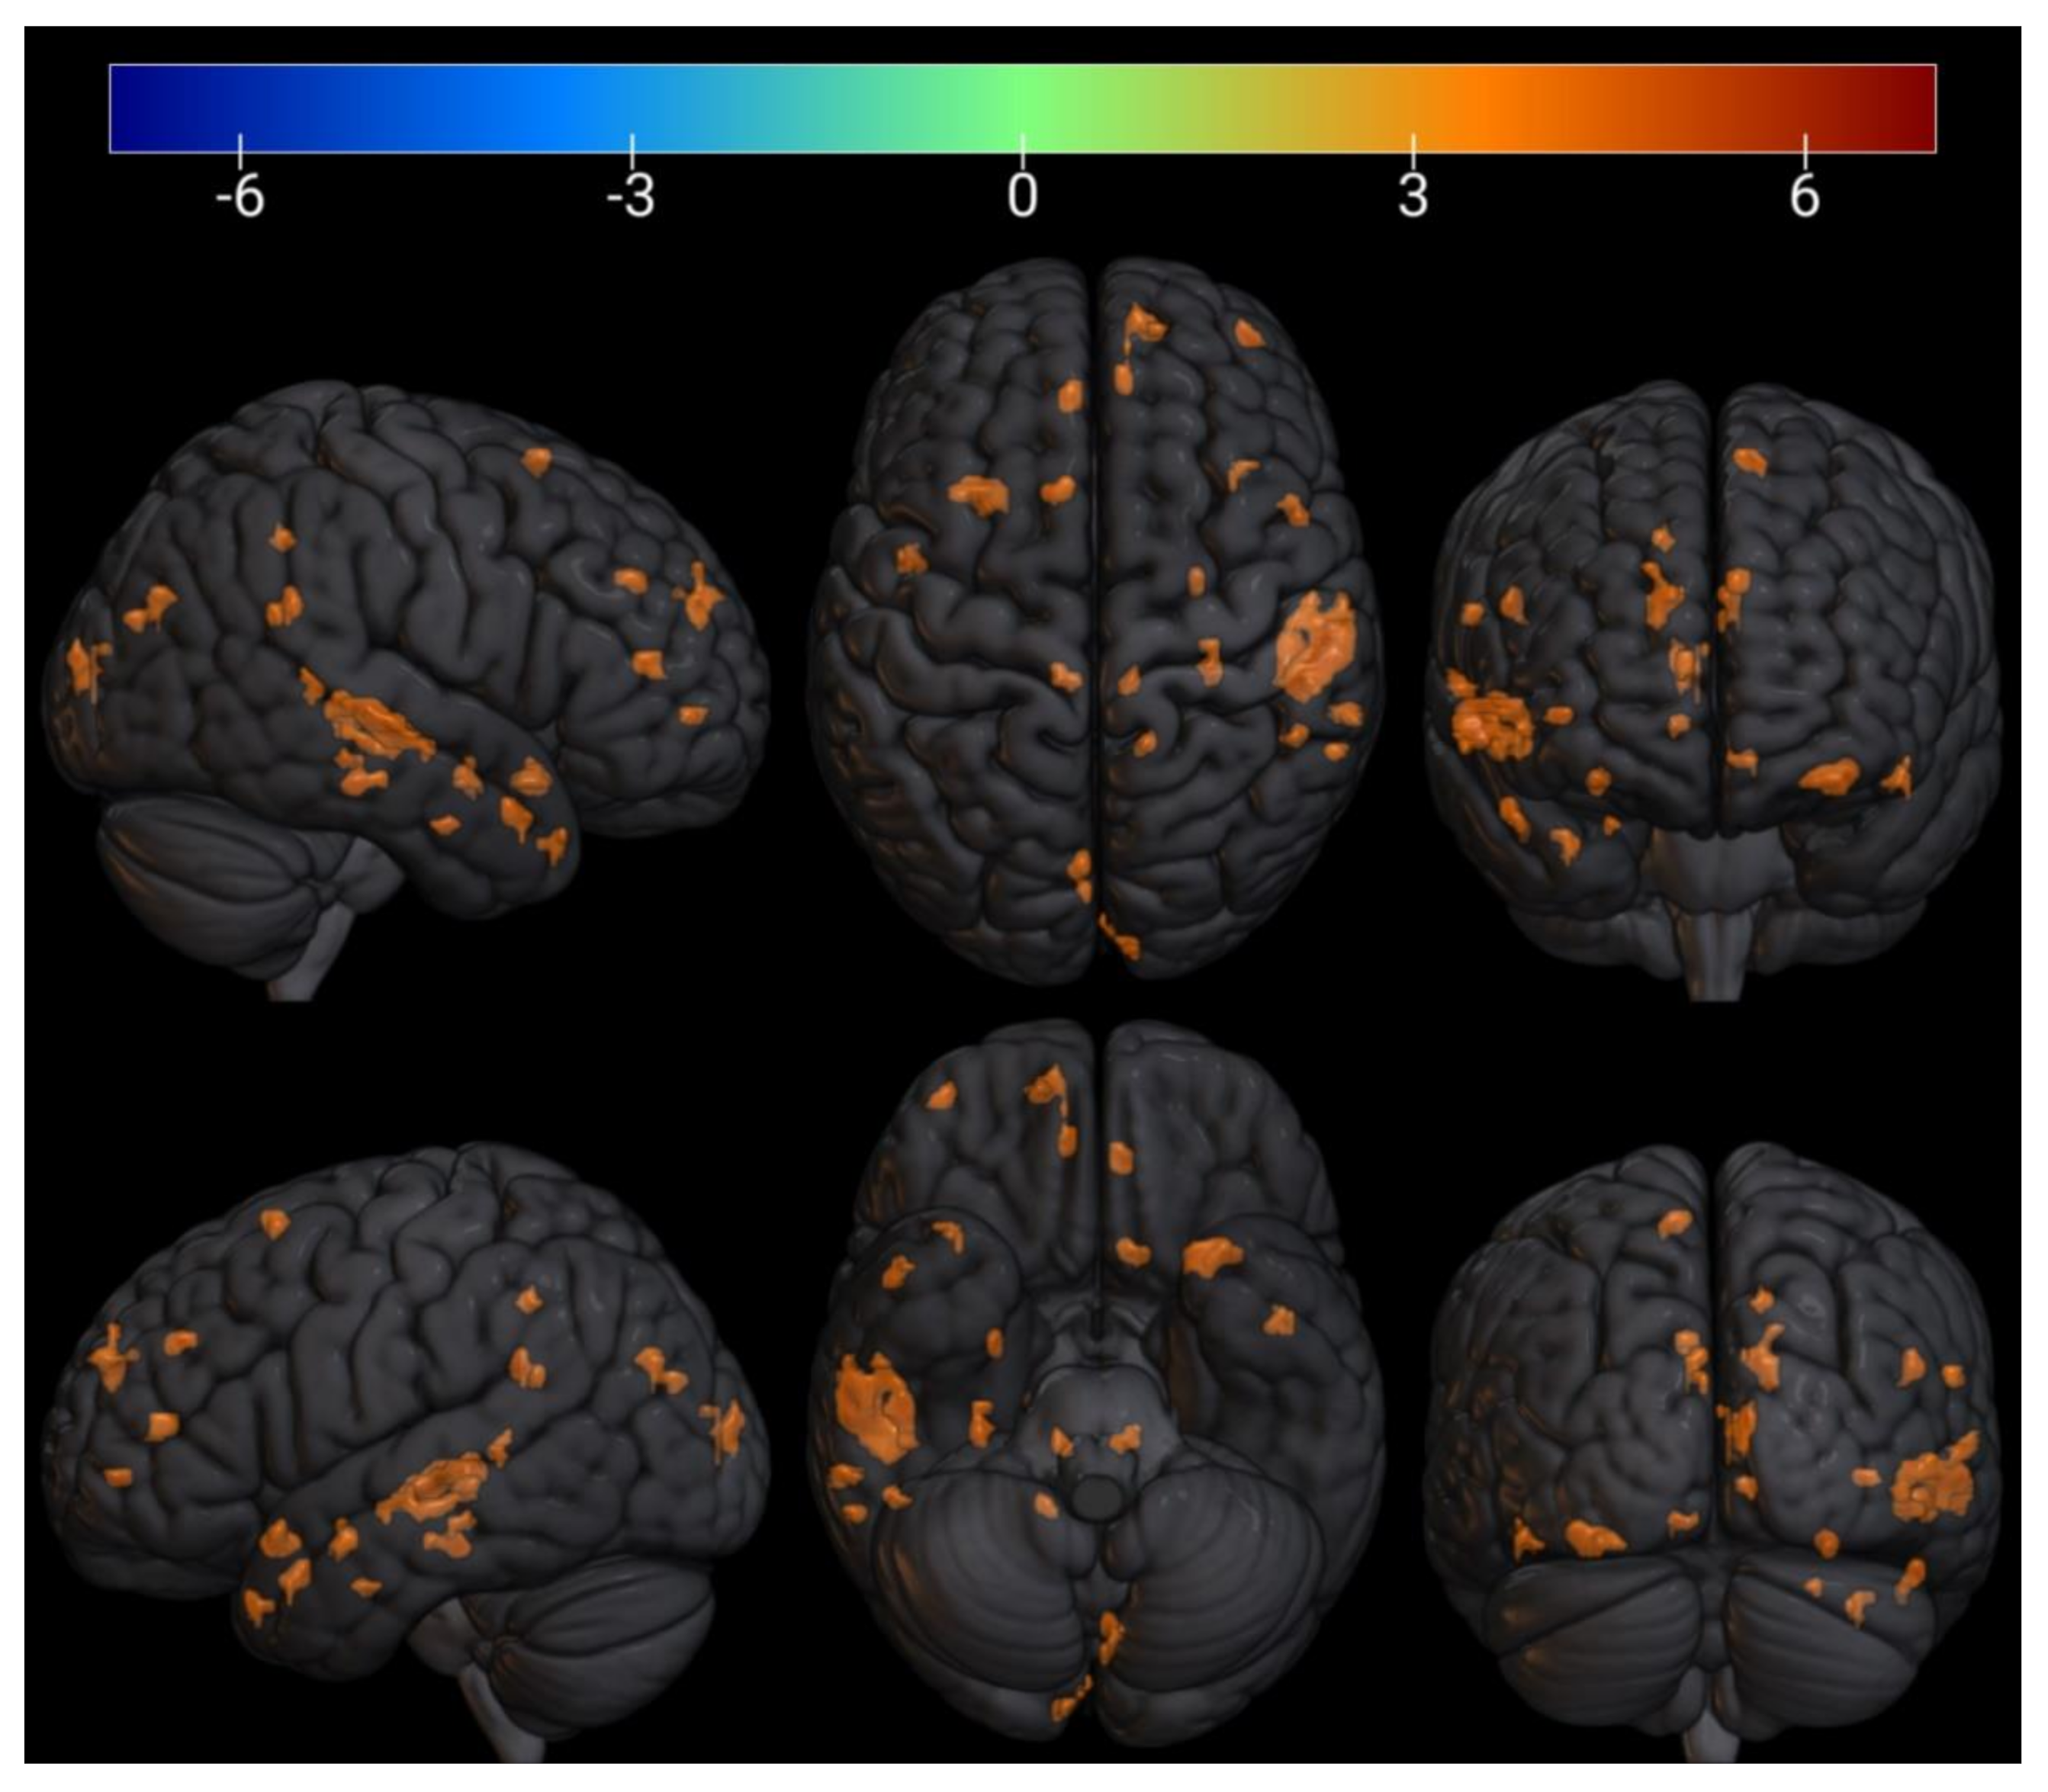

3.3. FMRI Analysis